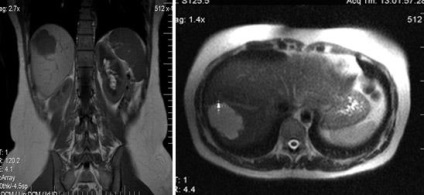

Natív és postkontrastnye MR hemangioma diffúz típusú amplifikációs.

MRI az UCP natív és dinamikus kontrasztos tanulmány. MRI dinamikus kontrasztanyagos megbízhatóan érzékeli, és lehetővé teszi egyedi képződése jellemzi a máj, mint a csomóponti noduláris hiperplázia.

Noduláris hiperplázia Máj